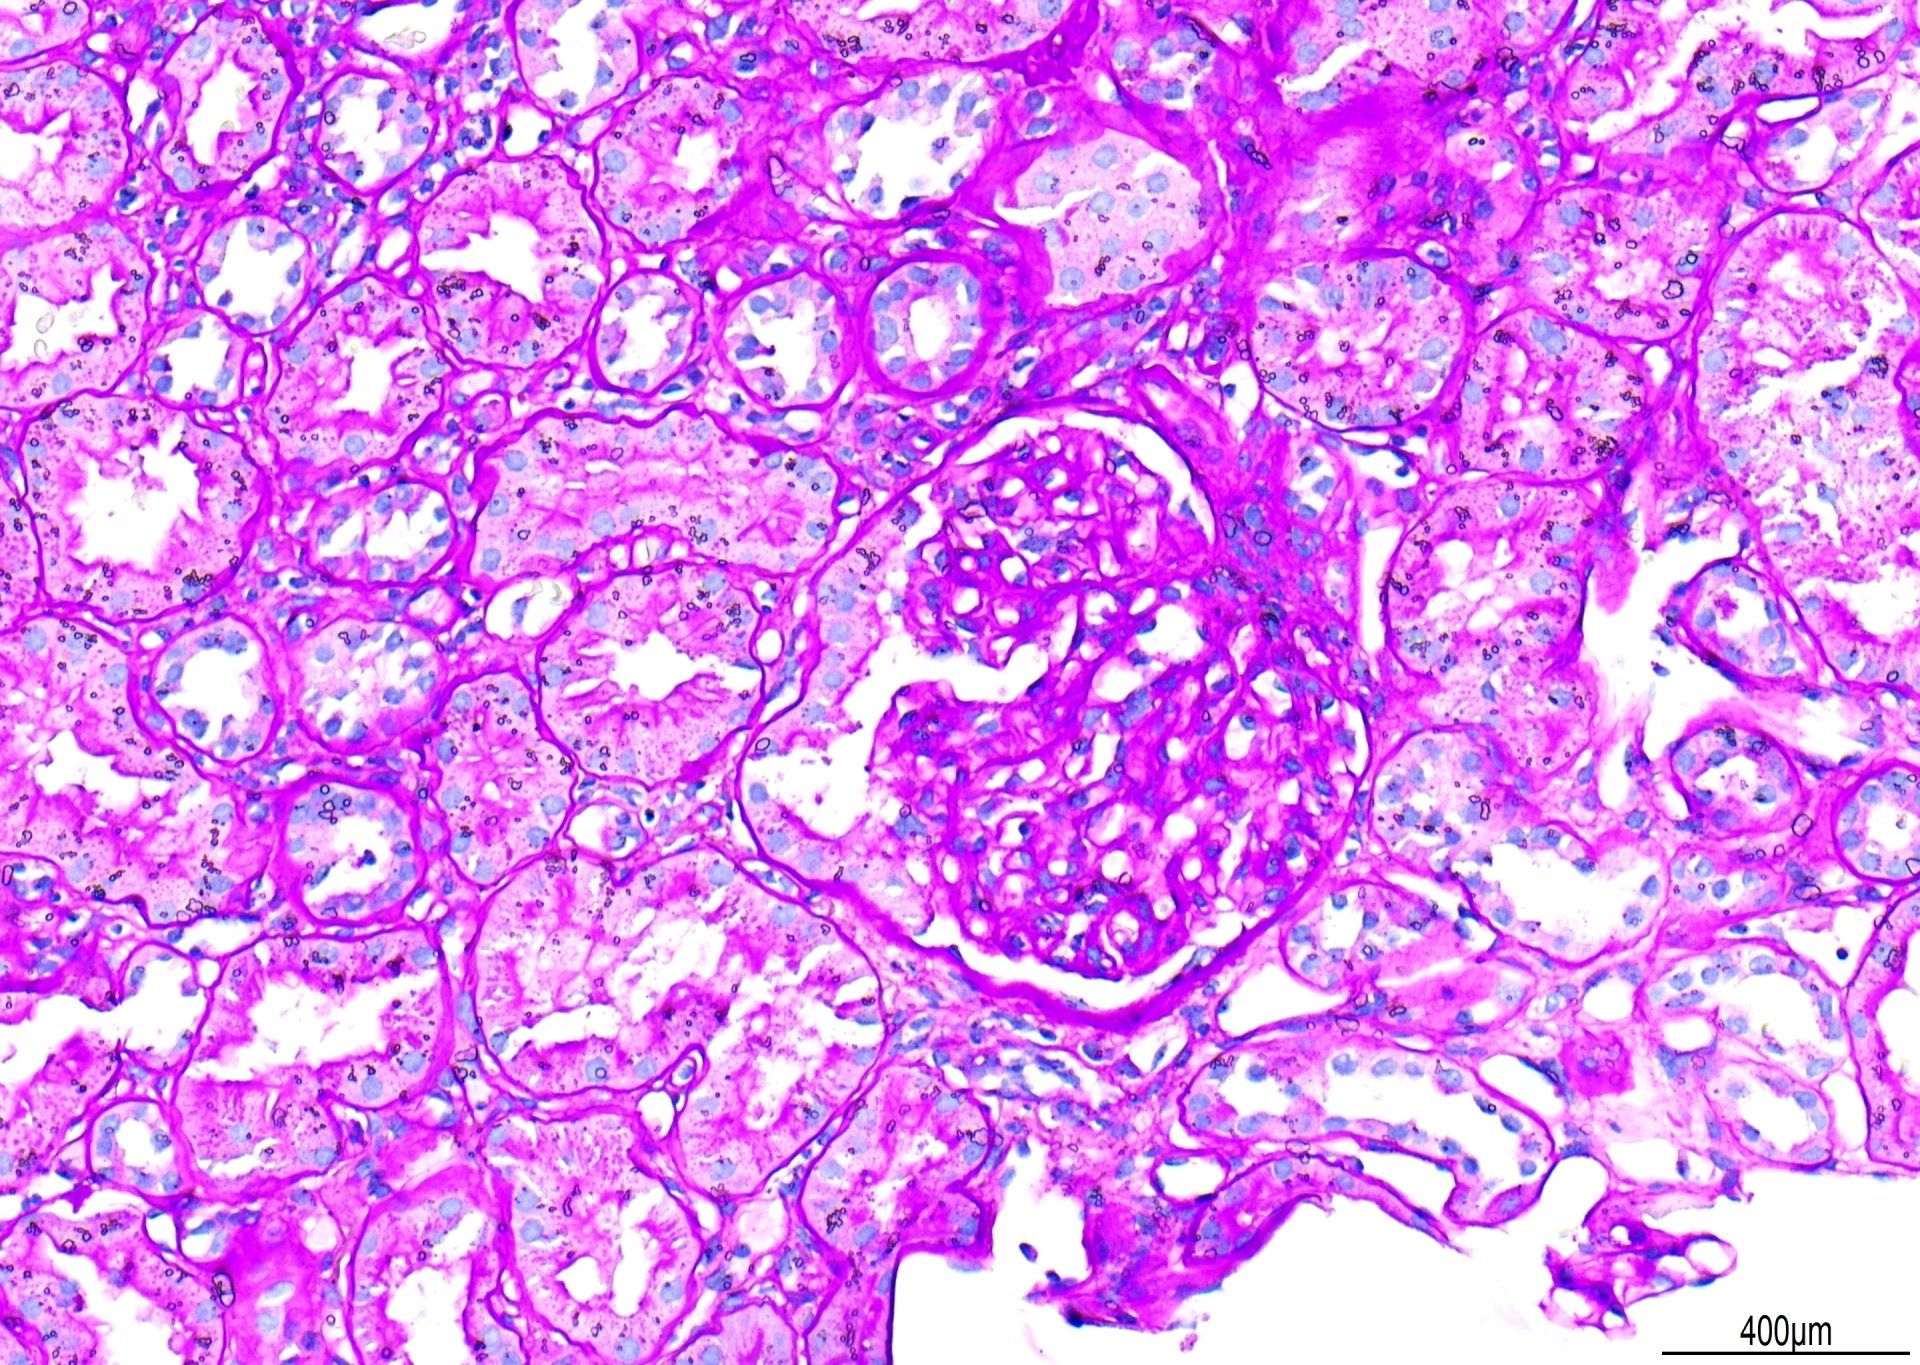

PAS - Esquema Renal

Vista a 20 aumentos, este es un ejemplo de tinción PAS. Se restaron puntos por la tinción de fondo primaria. Aunque las membranas basales glomerulares están bien teñidas, el contraste podría ser mejor si hubiera menos tinción de fondo de Schiff. Además, se observaron gotas de agua bajo el cubreobjetos. La puntuación general de esta sección fue de 7/10.